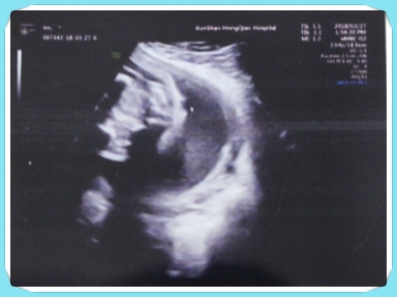

病情描述:胎儿骶尾部合拢呈截断性,未见明显裂开,皮肤纹理清晰,隐性脊柱裂不除外 最佳回答 因不能面诊,

孕24周湖南省妇幼四维彩超:胎儿脊柱第3、4、5骶骨椎体胎儿脊柱骶尾部,脊髓圆锥声像异常,不排除隐性脊柱裂

从你的描述来看,这个情况是询问这个超声是否可以诊断这个脊柱裂的情况的。这个是可以的,如果这个位置很好